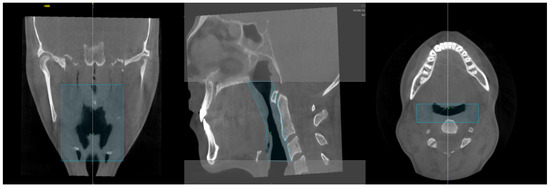

2.1. Airway Volume Calculation

2.2. Condyle Volume Calculation